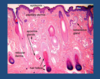

Outline the basics of skin histology

In hairy skin, there are hair follicles

Sebaceous glands make sebum which lubricates the hair and contains chemicals which suppress growth of bacteria and fungi

Outline the skin histology of the epidermis

Melanocytes are dark ones at bottom and look vaculated

Top-layer = weave-like structure = stratum corneum